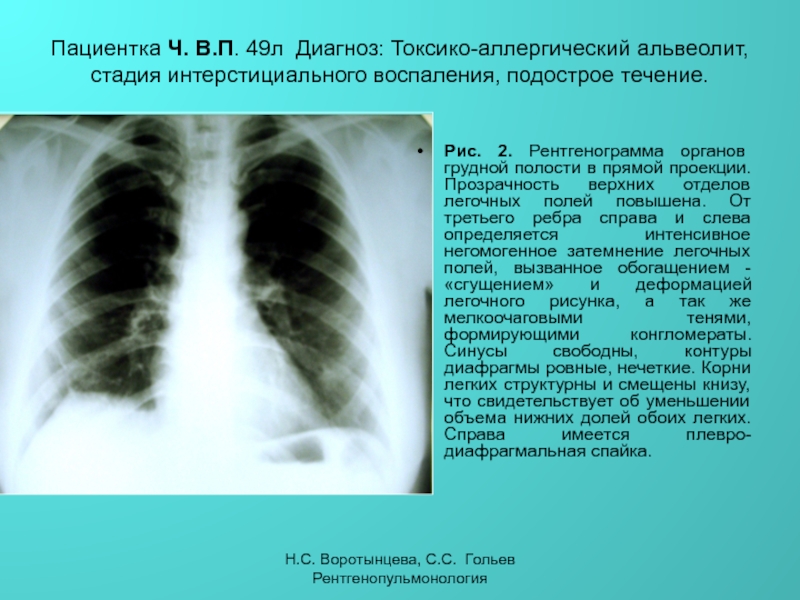

Ячеистая деформация легочного рисунка: медицинская визуализация